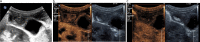

Gallbladder polyps are protuberances of the gallbladder wall projecting into the lumen. They are usually incidentally found during abdominal sonography or diagnosed on histopathology of a surgery specimen, with an estimated prevalence of up to 9.5% of patients. Gallbladder polyps are not mobile and do not demonstrate posterior acoustic shadowing; they may be sessile or pedunculated. Gallbladder polyps may be divided into pseudopolyps and true polyps. Pseudopolyps are benign and include cholesterolosis, cholesterinic polyps, inflammatory polyps, and localised adenomyomatosis. True gallbladder polyps can be benign or malignant. Benign polyps are most commonly adenomas, while malignant polyps are adenocarcinomas and metastases. There are also rare types of benign and malignant true gallbladder polyps, including mesenchymal tumours and lymphomas. Ultrasound is the first-choice imaging method for the diagnosis of gallbladder polyps, representing an indispensable tool for ensuring appropriate management. It enables limitation of secondary level investigations and avoidance of unnecessary cholecystectomies.